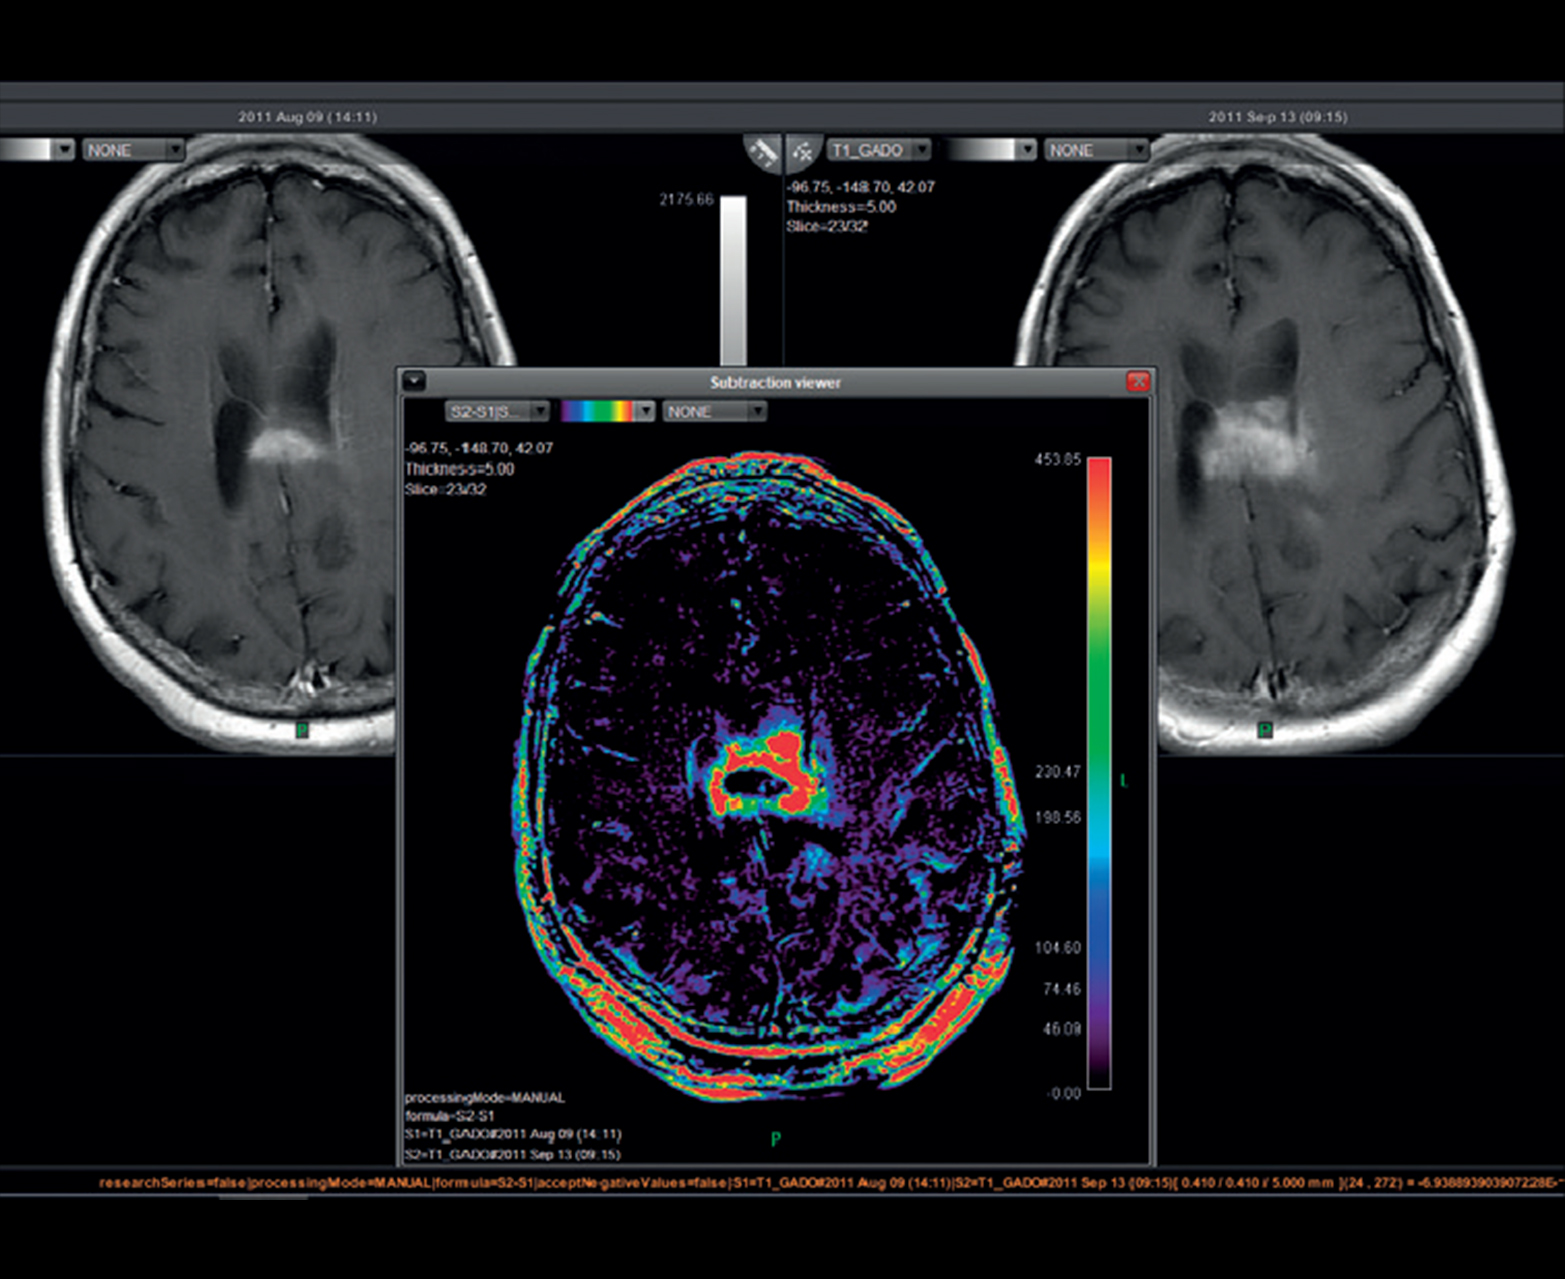

- Последующее наблюдение за развитием поражения и анализ ответа на лечение с временным вычитанием

Последующее наблюдение за поражением с совместной регистрацией